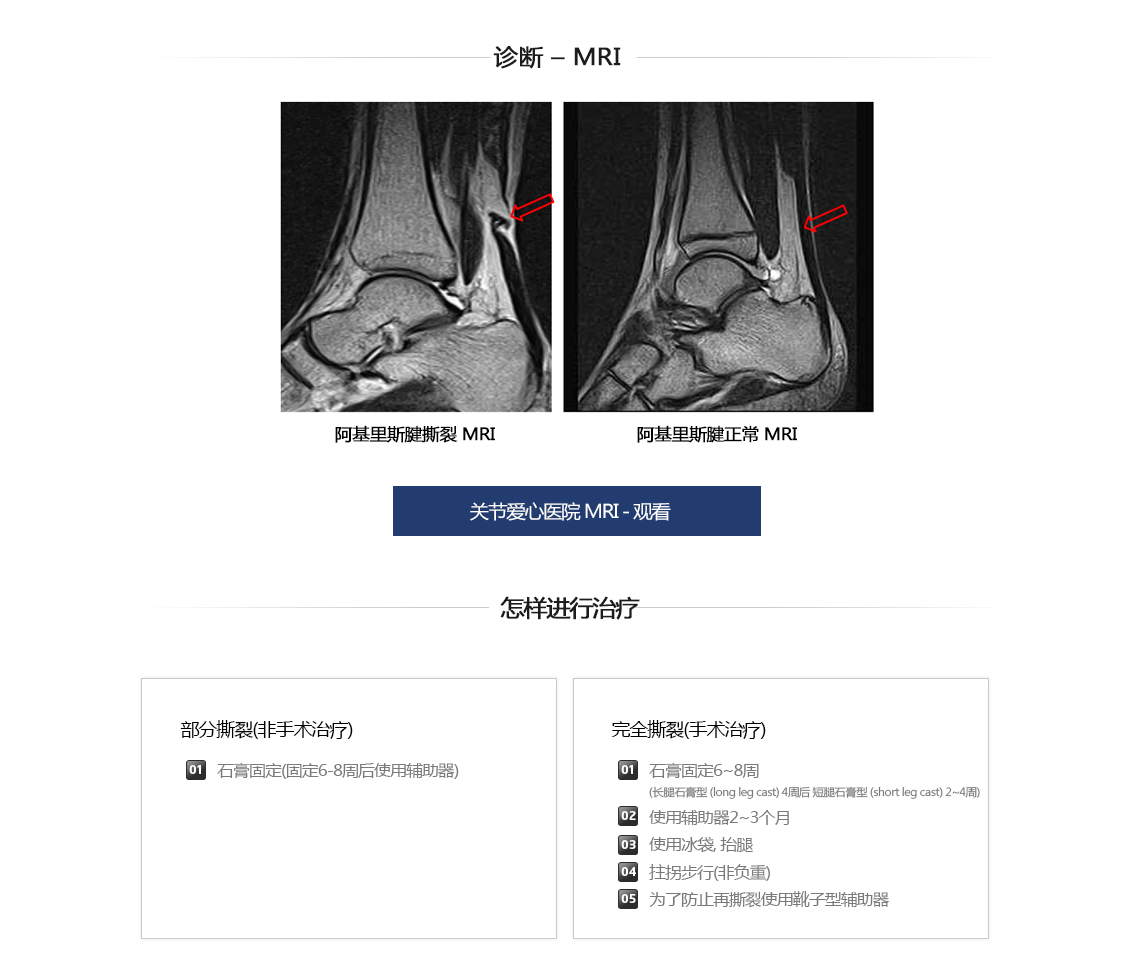

阿基里斯腱损伤及断裂